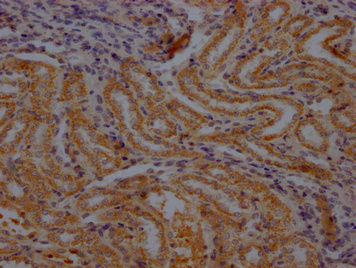

IHC image of PACO64491 diluted at 1:100 and staining in paraffin-embedded rat kidney tissue performed on a Leica BondTM system. After dewaxing and hydration, antigen retrieval was mediated by high pressure in a citrate buffer (pH 6.0). Section was blocked with 10% normal goat serum 30min at RT. Then primary antibody (1% BSA) was incubated at 4°C overnight. The primary is detected by a Goat anti-rabbit polymer IgG labeled by HRP and visualized using 0.05% DAB.